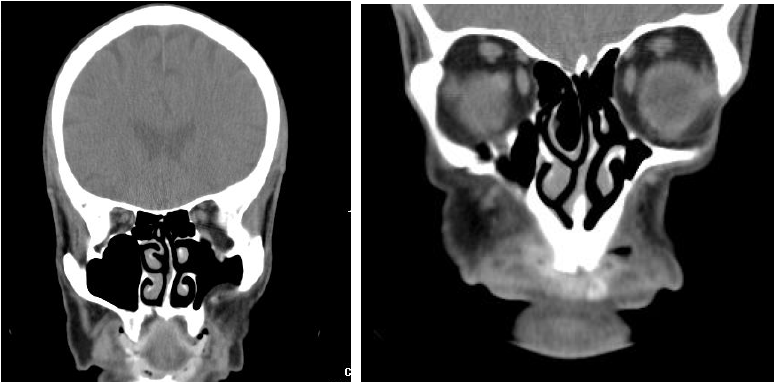

En la tomografía axial computarizada se observó una reducción de las partes blandas de la región maxilomalar derecha, con atrofia del seno maxilar del mismo lado, con disminución de sus partes óseas, y desviación del septum nasal hacia el lado derecho, (Figuras 4 y 5).